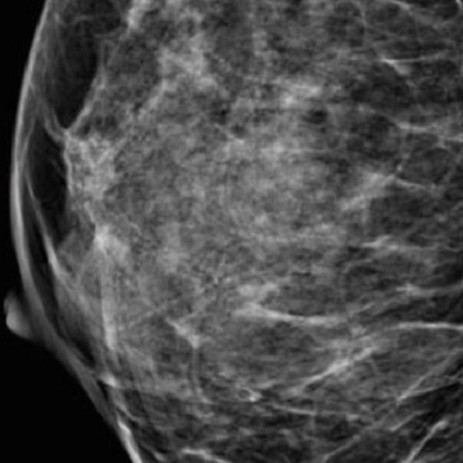

Аномалии молочной железы: медицинские примеры и визуализация

Раздел: Мудрость в деталях